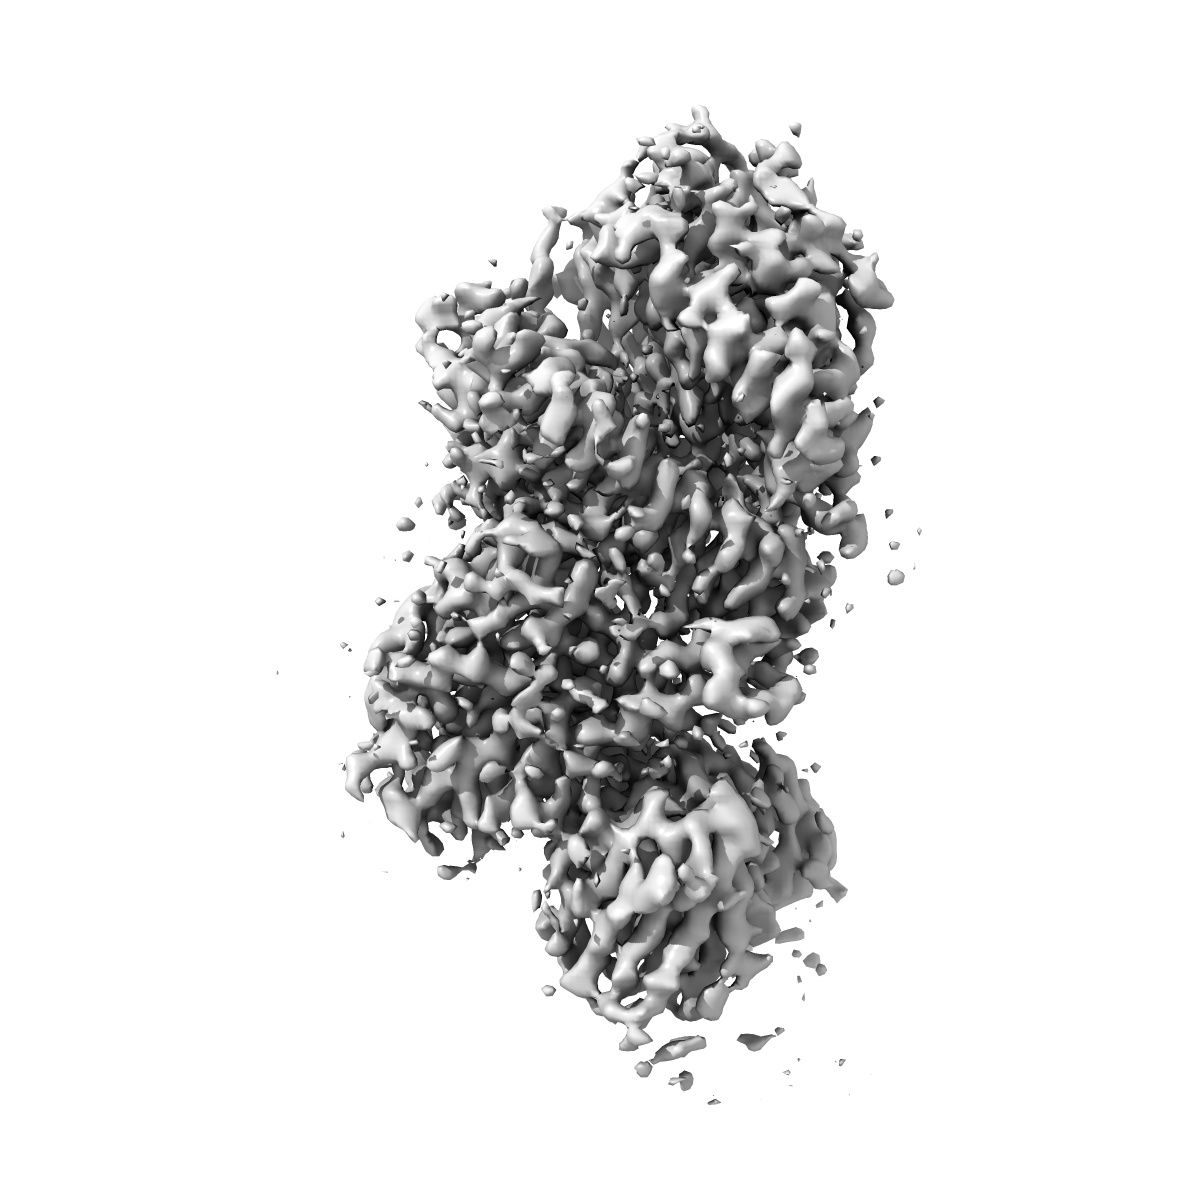

EMD-37779

XBB.1.5 RBD in complex with ACE2

Single-particle3.36 Å

Sample: SARS-CoV-2

Fitted models: 8wrl

Convergent evolution of SARS-CoV-2 XBB lineages on receptor-binding domain 455-456 synergistically enhances antibody evasion and ACE2 binding.

(2023) PLoS Pathog , 19 , e1011868 - e1011868